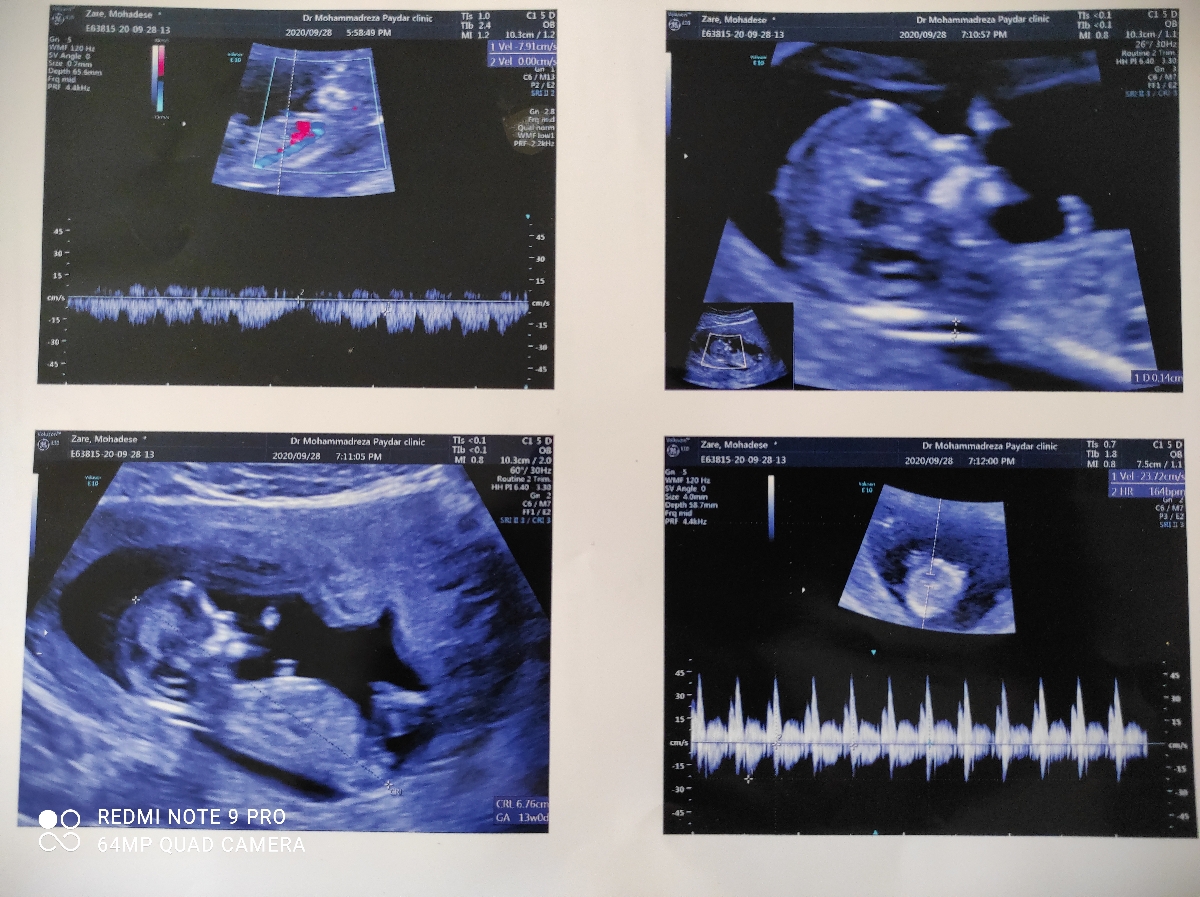

من طبق سونوی قلب دیروز که نوبت ان تی داشتم یازده هفته و هفت روز بودم...یا همون دوازده هفته تکمیل

اما دیروز که سونو دادم به من گفتن سیزده هفته ای اما اندازه crl. جنینم رو 67mmزدند

میشه بررسی کنید توی این هفته مگ نباید اندازه crl بیشتر باشه ممنون میشم جواب بدید ..و آیا درباره جفت چیزی نوشته که چجوری هست؟

عزیزم در سونوگرافی شما تمام موارد بررسی شده شامل وضعیت جنین،حجم مایع آمنیوتیک و طول سرویکس همگی طبیعی بوده و مشکلی ندارد. اندام ها و ارگان های مورد بررسی دلبندتان نیز کاملا طبیعی هستند و CRL مشکلی ندارد. در واقع اختلاف یک تا دو هفته در سن بارداری مهم نبوده و جای نگرانی ندارد.

در رابطه با جفت هم محل آن دیواره جلویی رحم متمایل به چپ گزارش شده که طبیعی است.

مجموعا نتیجه سونوگرافی عالی است جانم و باید منتظر بخش آزمایش خون غربالگری باشیم 🌹🌹🌹